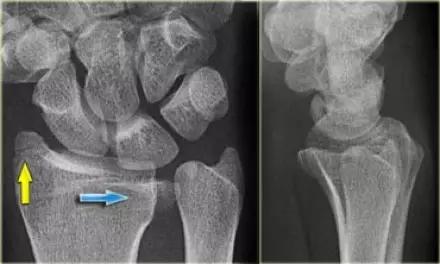

4. Die-punch 骨折

远端桡骨的关节内骨折,伴有月骨陷窝背侧表面的压迫。也称月骨负荷骨折或模具冲压骨折,指挠骨的月骨对应面发生的向近侧的压缩骨折,有不与周围关节囊相连的游离关节面骨折块。

Die-punch 骨折(来源:radiology assistant)